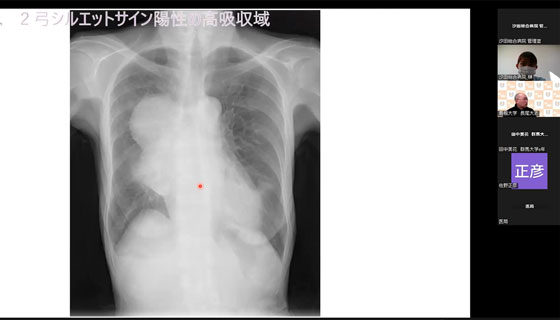

(CFMD家庭医療学開発センター センター長 藤沼康樹先生) - 「シルエットサインマスター講座シリーズ」

(島根大学地域医療教育学講座教授 長尾大志) - 「明日からも学んでみたくなる漢方」